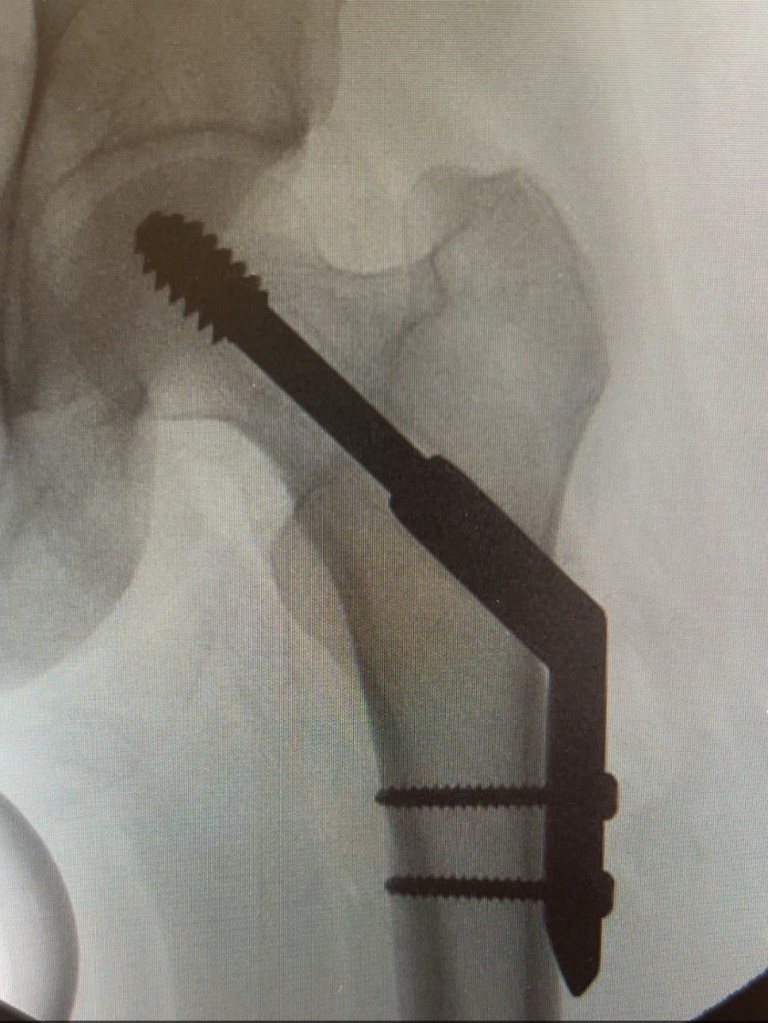

Beðið eftir aðgerð Það var strax tekin ákvörðun um aðgerð, enda er þetta brot flokkað sem bráðatilvik. Ég átti að fara í aðgerð strax í vikunni og var send heim á hækjum. Mátti alls ekki stíga í fótinn (sem mér þótti alveg galið) og átti að hafa mjög hægt um mig. Ég fór í veikindaleyfi og fastaði þar til ég var tekin í aðgerð.

Fyrst var mér sagt að þetta væri tiltölulega lítið mál og ég yrði send heim samdægurs. Tvö lítil göt, tvær skrúfur og plástur á meiddið. En svo varð þetta töluvert flóknara: Nagli í kúluna með áfastri plötu og tveimur skrúfum.

Það var gerð mænudeyfing og létt svæfing og aðgerðin tók ekki langan tíma og gekk vel að sögn læknisins. En ég var ekkert farin á fætur beinlínis eftir nóttina og var afar verkjuð. Ég endaði á að vera þrjár nætur á Borgarspítalanum og kom heim á fjórða degi.